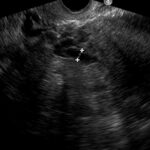

Fig. 2: a) Examen ecográfico por vía transvaginal, que muestra vena ovárica izquierda ectásica de 7.5 mm. b) Examen ecográfico por vía transvaginal, demostrando vena ovárica derecha normal, de 2.5 mm.

Hallazgos imagenológicos. En el eco Doppler ginecológico por vía transvaginal se observa varicocele pelviano (Fig. 1). La vena ovárica derecha mide 3.8 mm, y la izquierda, ectásica, 7.4 mm (Fig. 2). En el eco Doppler abdominal se visualiza la vena renal izquierda, de 3.1 mm en topografía del compás aorto-mesentérico y 8.1 mm en el segmento proximal al riñón izquierdo, con una velocidad 50cm/s en el compas y 30cm/s en el segmento proximal al riñón. El estudio corresponde en primera instancia a un síndrome de Nutcracker (Fig. 3).